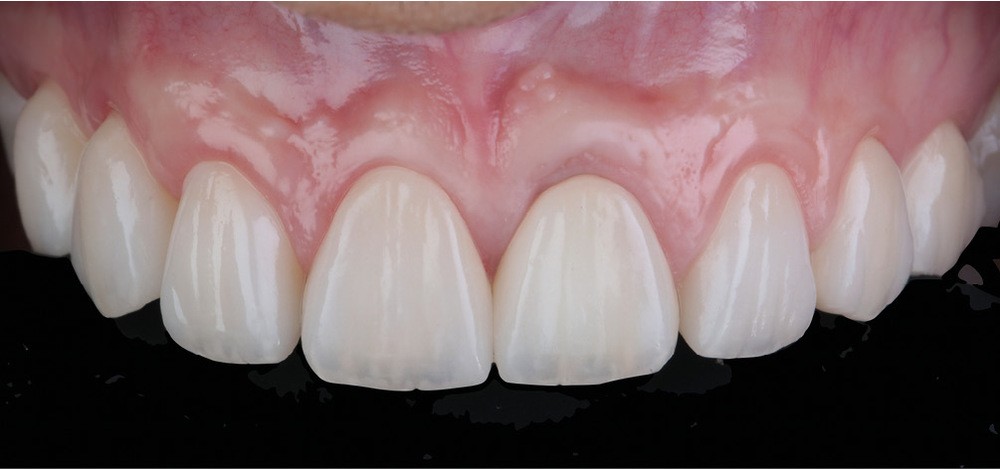

Acte 6 : assemblage et résultat (fig. 9 et 10)

Nous assemblons les céramiques selon la technique choisie (scellement pour les couronnes et collage pour les facettes). Le patient est revu à quinze jours pour contrôle de la cicatrisation.